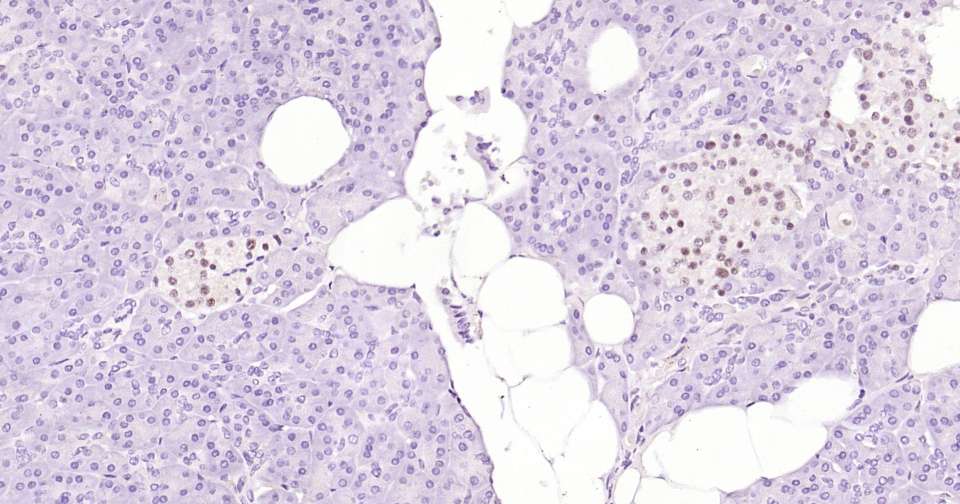

Immunohistochemical analysis of paraffin embedded rat pancreas tissue slide using IHC0367 (PAX6 Kit).